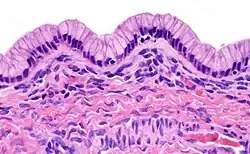

| High magnification micrograph of a Brenner tumor, a type of surface epithelial-stromal tumor. H&E stain. | |

Pathology

Mucinous tumors are characterized by a lining of tall columnar epithelial cells with apical mucin and the absence of cilia, similar in appearance with benign cervical or intestinal epithelia. The appearance can look similar to colonic or ovarian cancer, but typically originates from the appendix (see mucinous adenocarcinoma with clinical condition Pseudomyxoma peritonei). Clear stromal invasion is used to differentiate borderline tumors from malignant tumors.